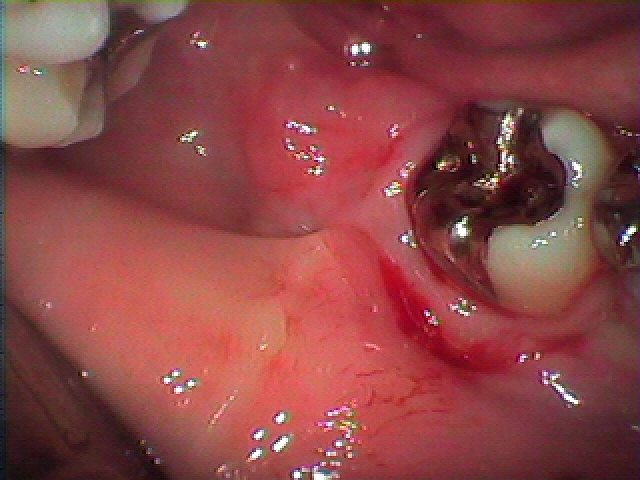

抜けにくい親不知の1つかと思います。| |広島市安佐南区の歯科医院 抜けにくい親不知の1つかと思います。 トップ お知らせ・ブログ 抜けにくい親不知の1つかと思います。 抜けにくい親不知の1つかと思います。 Web診療予約 初めての方へ 選ばれ続ける理由 院内設備について 歯が痛いしみる一般歯科 歯がぐらぐらする歯周病 健康な歯を保ちたい予防歯科 子供の虫歯予防をしたい小児歯科 銀歯をセラミックに審美歯科 白い歯を目指しませんか?ホワイトニング 矯正専門医がいるので安心矯正歯科 抜けた歯を補いたいインプラント・入れ歯 医院案内 スタッフ紹介 メリィハウス歯科クリニックオフィシャルホームページ ラベンダー歯科クリニックオフィシャルホームページ お知らせ・ブログ ホーム 診療科目 一般歯科 歯周病治療 予防治療 小児歯科 審美治療 ホワイトニング 矯正歯科 入れ歯・インプラント マウスピース矯正 初めての方へ 院長・スタッフ 設備紹介 医院案内・アクセス メニューを閉じる